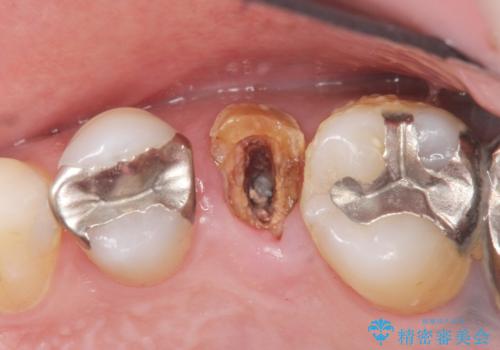

- 奥歯のかぶせ物が土台ごとはずれてしまったことを主訴に来院された患者様です。

残根状態になっている左上の小臼歯(左上5)を精査したところ、う蝕が歯肉縁下まで進行しており保存不可能な状態でした。